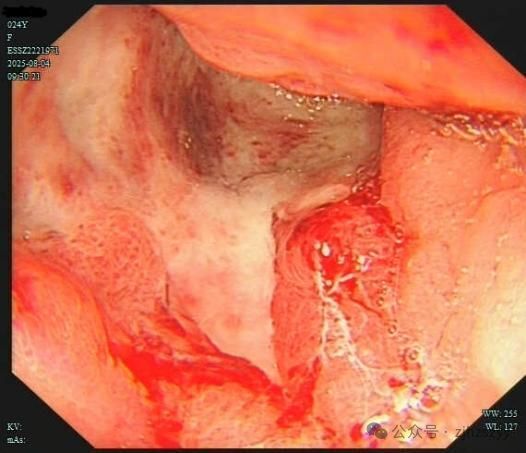

直到她开始频繁出现黑便,并在片场拍戏时几次呕血,才被同事紧急送往我院急诊。情况紧急,医生立即为小雯安排了急诊胃镜检查,发现她整个胃窦被一巨大的溃疡占据,黏膜组织变得僵硬、缺乏弹性,好似“皮革”一般。而随后的活检结果,更是给了这个年轻姑娘沉重一击——胃印戒细胞癌。

胃印戒细胞癌早期的隐匿性很强,在胃镜下表现也不明显,识别非常困难,可能表面看起来只是点、片状糜烂,而实际上已经多点生长。